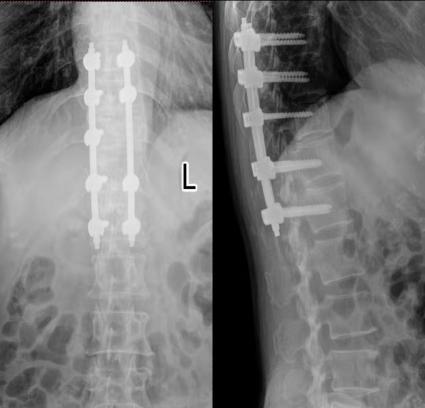

术后复查x线、CT

术后患者背部疼痛消失,双侧足底麻木感逐渐缓解,没有出现任何并发症,术后第二天拔除引流管,在支具保护下行走,术后第七天出院。

患者出院1周回院复查,外固定支具保护下地行走无任何问题,双侧足底麻木感消失,谭院长对患者术后康复从饮食及运动等多个方面进行了亲切的指导,患者及家属对潍坊市中医院东院区脊柱骨科全体医护人员不辞辛苦的努力表示感谢,合影留念。